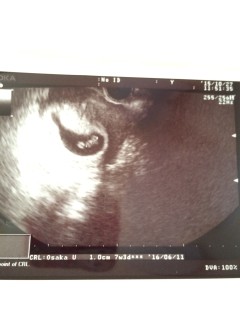

一週間ぶりの検診。 エコー写してる時間が短くて心拍は見れなかったけど、前回の6ミリから1cmまで大きくなっていました。 前回は見えなかった卵黄嚢もハッキリ見えて、赤ちゃんもよーく見ると目のようなものが見えて感動。 排卵日から計算すると8w0dですが、胎芽の大きさから7w3dと言われました。 母子手帳の説明は二週間後です。 でも、分娩の病院の予約をすぐ取り一安心です。 二週間後、どれくらい大きくなっているか楽しみです。